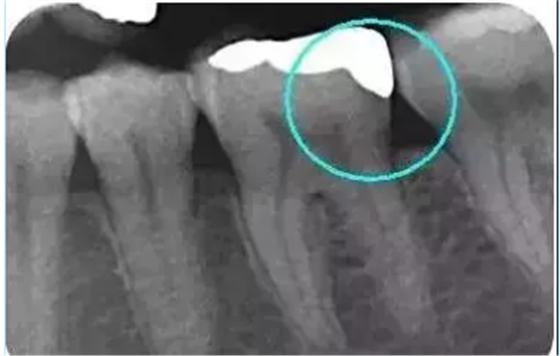

從下面這張X線中可以看出,嵌體遠(yuǎn)中邊緣沒有懸突,與牙體邊緣密合相接。